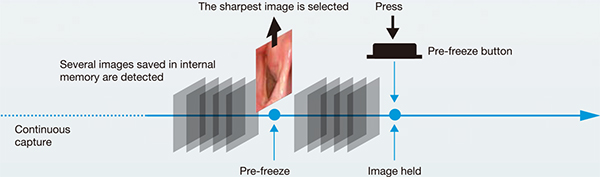

Pre-freeze Function

The scope continuously captures stil images even before youpush the Pre-freeze button. When you press the button, thesystem automatically selects the sharpest image amongseveral.